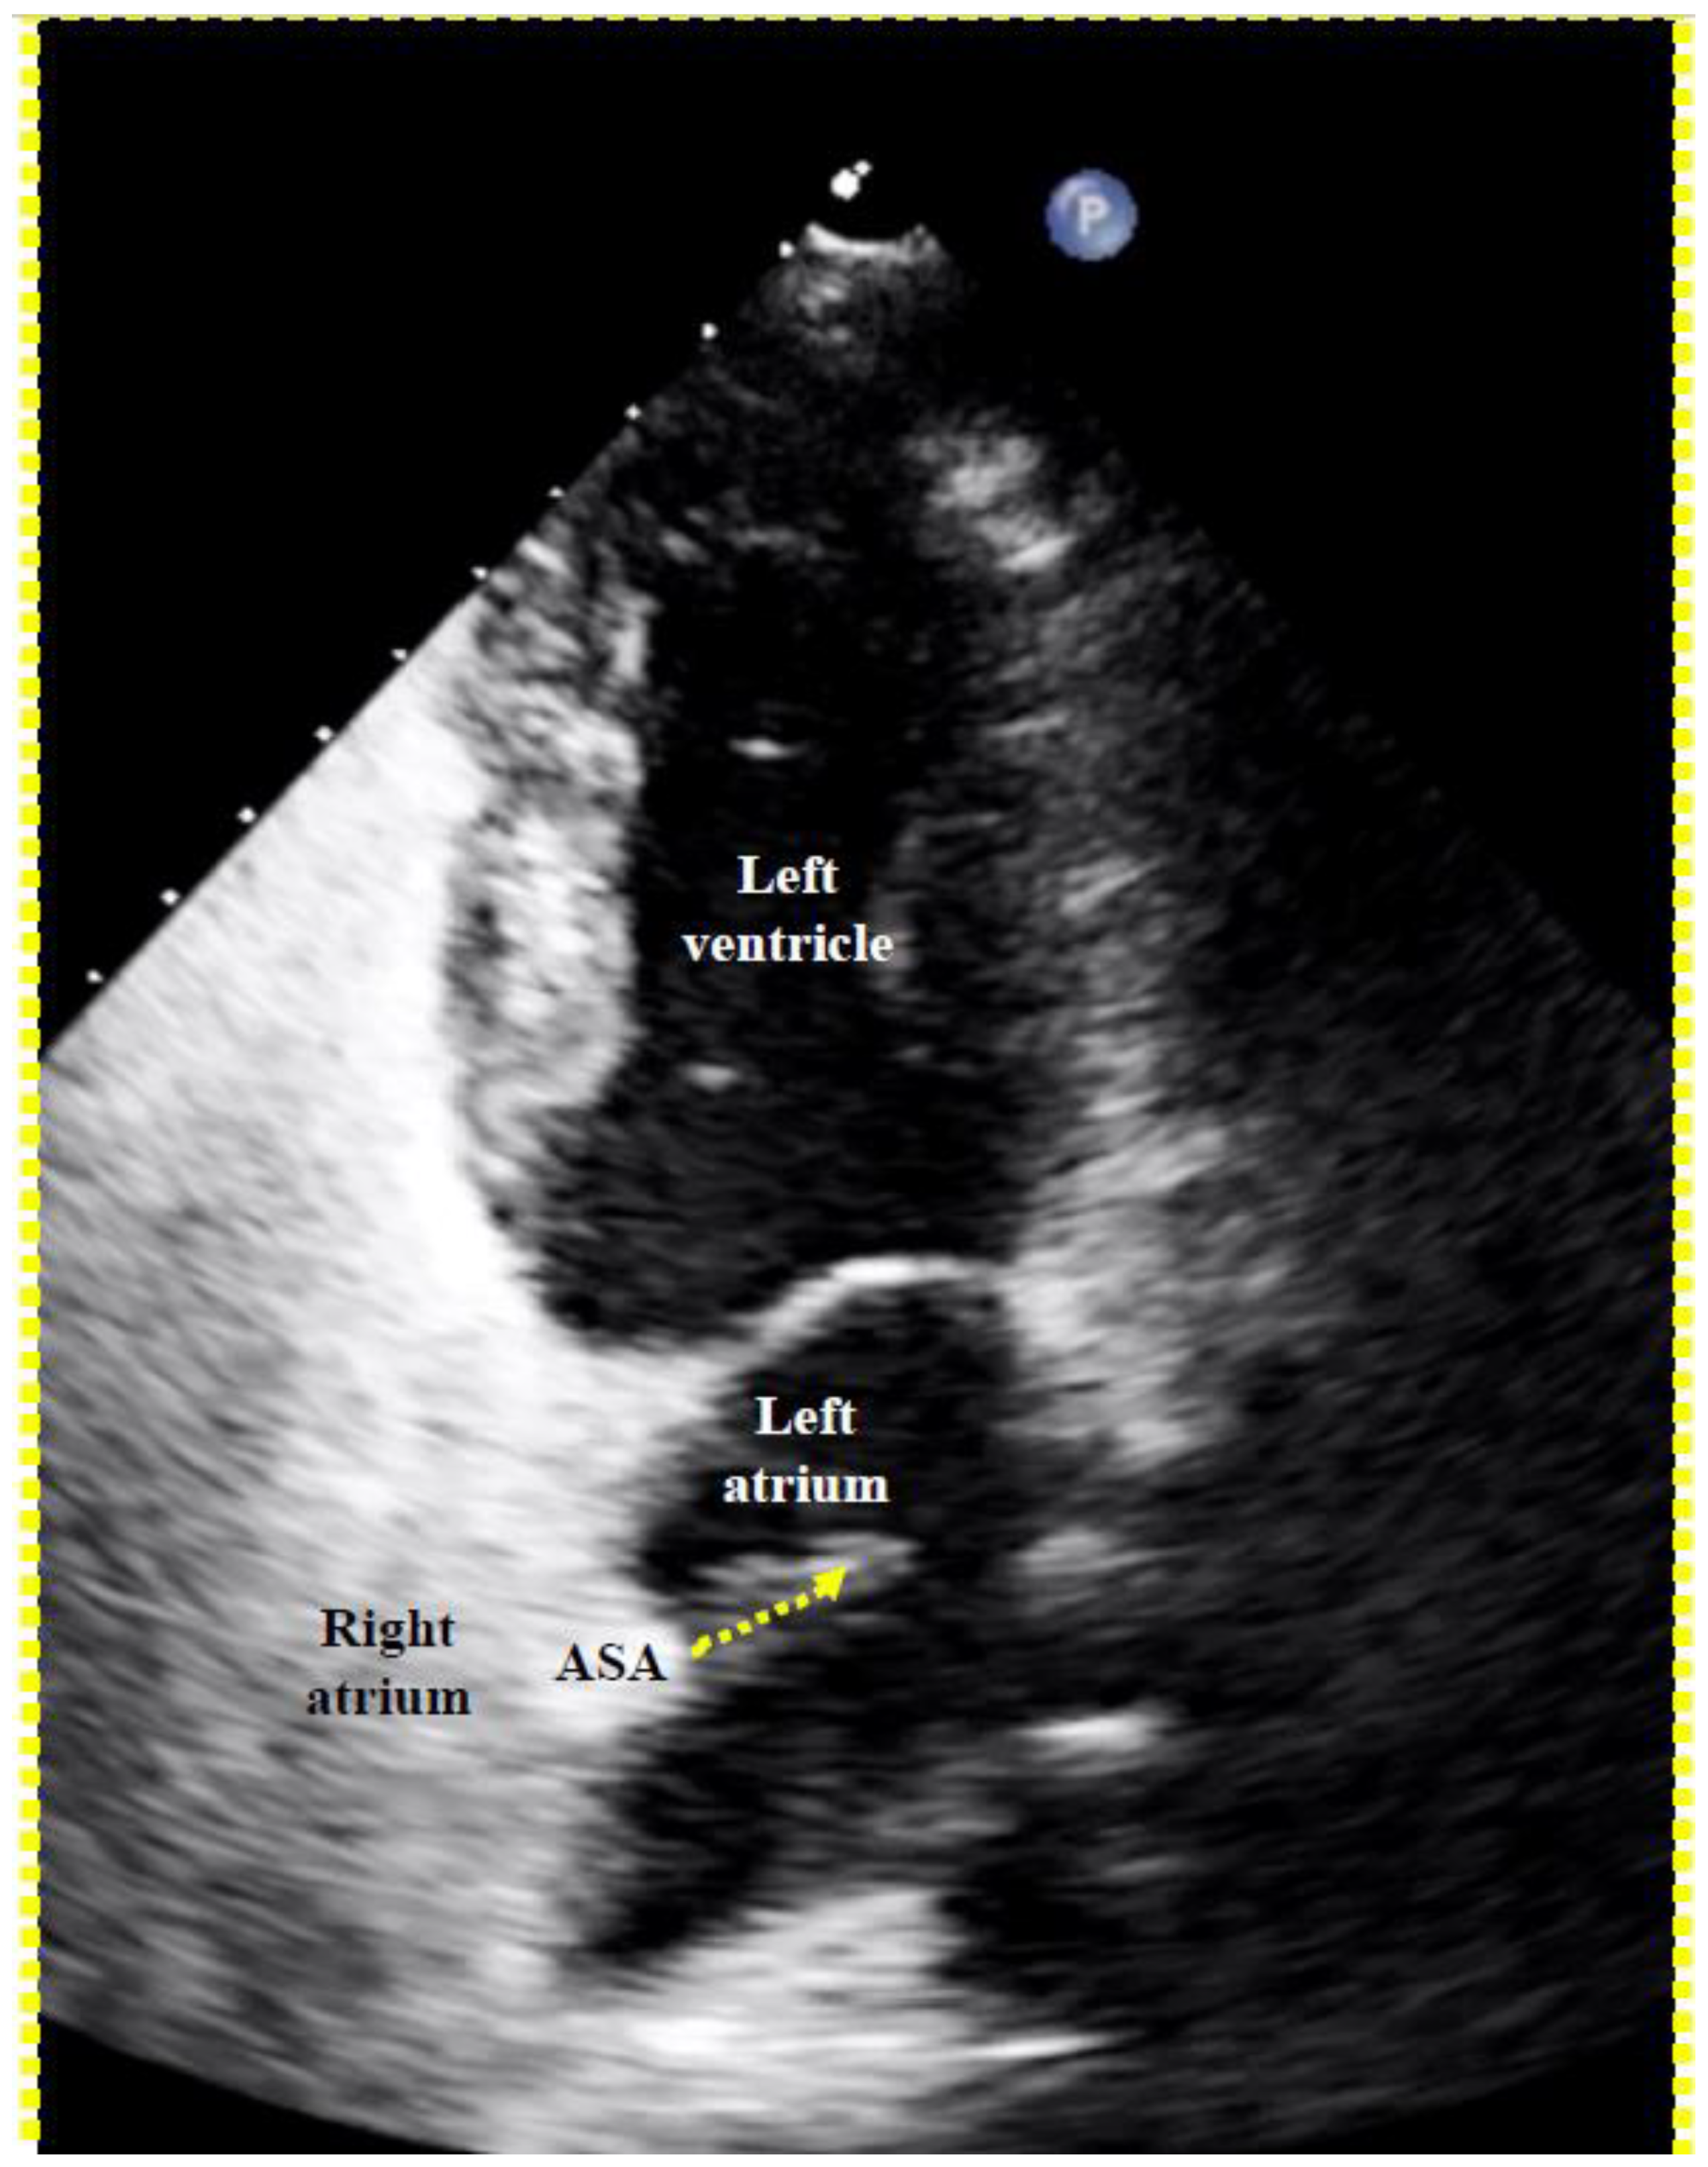

To screen for dangerous PFOs, i.e., large ones or those associated with an ASA [8], a Eustachian valve [9,10,11,12], or a Chiari network [13], a bubble test during a TTE suffices (Figure 5). The contrast liquid has to be injected at the end of a sustained Valsalva maneuver. A Valsalva maneuver, or pressing into the upper belly by a medical person during TEE if a sedated patient cannot perform a Valsalva maneuver, blocks the backflow of the venous blood into the thorax. Both atria become volume-depleted within 10 to 20 s. Upon Valsalva or pressing release, the venous blood gushes into the right atrium first, thereby pushing the PFO open towards the still underfilled left atrium.

Figure 5.

Proof of a patent foramen ovale (PFO) with right-to-left shunt with transthoracic echocardiography. A right-to-left bubble shunt (dotted arrow) is demonstrated with its origin in the region of a conspicuous atrial septal aneurysm (ASA).

The venous inflow into the right atrium from the inferior vena cava is directed onto the PFO, even more so in the presence of a Eustachian valve [9,10,11,12] or a Chiari network [13]. The inflow of the superior vena cava is not. Hence, injecting the contrast medium in a leg vein would be ideal [14,15]. Yet this is impractical, and under most circumstances, an arm vein has to do. A state-of-the-art bubble test during a TEE or a transcranial Doppler examination [16] in addition detects small PFOs that harbour a smaller (albeit still relevant) risk for paradoxical embolism.